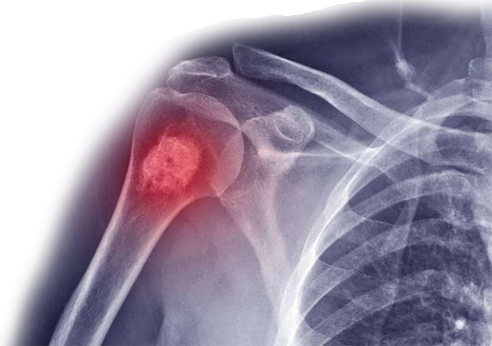

Whether the bone tumor is “Benign” or “Malignant” we are providing tailor-made treatments for our patients.

Malignant Bone Tumors:

- Osteosarcoma

- Ewing sarcoma

- Chondrosarcoma

Benign Bone Tumors:

- Osteochondromas

- Enchondroma

- Osteoid Osteoma

- Chondroblastoma

- Nonossifying fibroma

- Giant Cell Tumors

- Fibrous Dysplasia

- Aneurysmal Bone Cyst